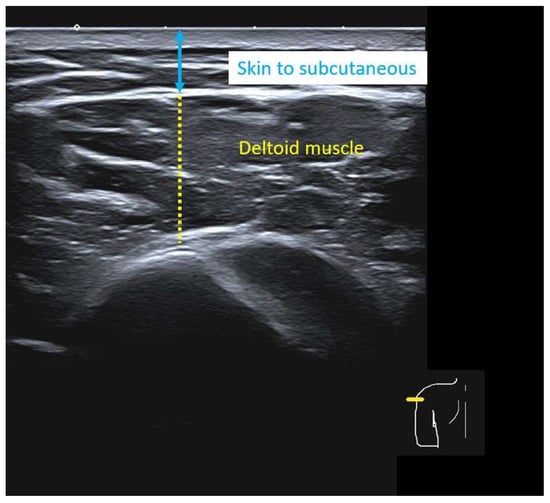

Individualized Deltoid Landmark and Needle Length for Safe Intramuscular Vaccination in Southeast Asian Adults: An Ultrasound Study

Background/Objectives: An incorrect intradeltoid injection technique can cause shoulder injury related to vaccine administration, including bursitis, septic arthritis, and axillary nerve injury, particularly when Western-derived landmarks and needle-length tables are applied to smaller-framed Southeast Asian adults. We aimed to define an individualized deltoid injection landmark and needle length that avoid the axillary nerve while ensuring reliable intramuscular delivery in Southeast Asian adults. Methods: In this cross-sectional ultrasound study of adults aged ≥18 years, four vertical landmarks below the acromion (individual contralateral 2-fingerbreadth (FB), individual contralateral 3-FB, average 2-FB, average 3-FB) were assessed in two arm positions (adduction and approximately 30° abduction with the hand on the waist). For each combination, we recorded the presence of the axillary nerve and measured skin-to-subcutaneous and deltoid muscle thickness to estimate whether 0.5-, 1-, or 1.5-inch needles would terminate within muscle or penetrate the subdeltoid bursa. Results: Eighty-two participants (39 males, 43 females) were included. The axillary nerve was not visualized at the individualized contralateral 2-FB landmark in adduction but was present at 31.7–50.0% of other landmark–position combinations. At the individualized 2-FB site in adduction, mean skin-to-subcutaneous thickness was <12.7 mm and mean skin-to-subdeltoid fascia distance exceeded 12.7 mm in all strata, implying that a 0.5-inch needle would consistently terminate within the deltoid muscle. Conclusions: In Southeast Asian adults, the contralateral individualized 2-FB landmark in arm adduction provides a neurovascularly safe window for intradeltoid vaccination, and a 0.5-inch needle offers reliable intramuscular delivery while minimizing the risk of bursal penetration. Full article

Figure 1